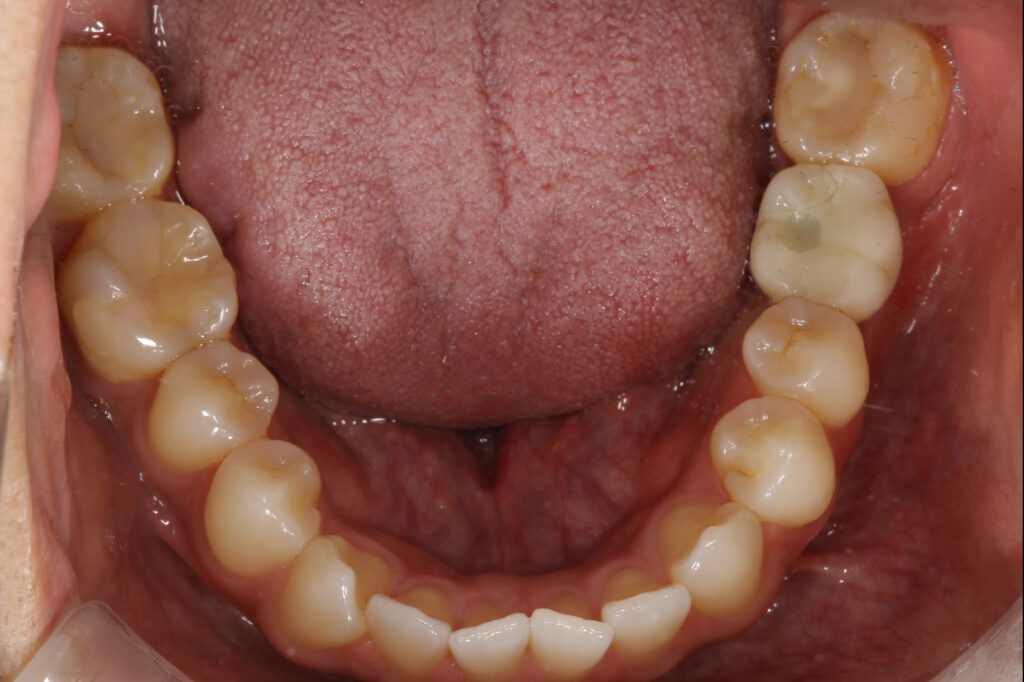

| 主訴 | 左下の被せ物のところの匂いが消えない。違和感があるので見てほしい |

| 年齢 | 20代男性 |

| 治療内容 | 歯質と補綴物の不適合あり。CT撮影を行って確認したが残すことが難しい為インプラント治療へ。 最終的なかぶせものはご自身の歯と変わらないような仕上がりとなっています。 |

| 抜歯部位 | 左下6 |